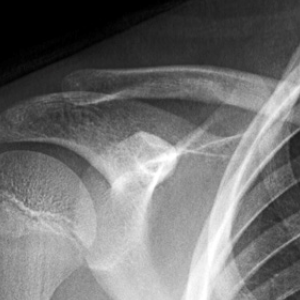

• Tips for Diagnosing Occult Fractures in the Emergency Department